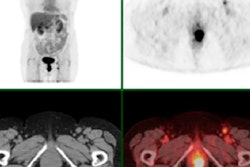

All patients underwent two FDG-PET/CT and two FMISO-PET/CT scans on the same scanner and under identical conditions. In 24 (70%) of 34 patients who had positive FMISO results, the radiotherapy dose was increased up to 86 Gy on hypoxic areas identified on FMISO-PET/CT. However, this additional dose did not improve patient outcomes (JNM, July 2017, Vol. 58:7, pp. 1045-1053).

At the three-month follow-up, 31 patients (57%) showed a favorable response to the radiotherapy, including 17 (50%) of the 34 patients in the FMISO-positive group. At one year, overall survival was 63%, and disease-free survival was significantly longer among patients whose FMISO scans were negative (p = 0.004). Radiotherapy dose, however, was not associated with disease-free survival when adjusted for patients' FMISO status.

Images from a patient with an upper left lung NSCLC. (A) FDG; (B) FDG-PET/CT; (C) planning radiotherapy based on FDG (66 Gy) with BTVm (gross tumor volume), clinical target volume, and planning target volume; (D) FMISO-PET; (E) FMISO-PET/CT; and (F) boost based on the FMISO-PET (76 Gy) with BTVh (biological hypoxic target volume) and planning target volume boost. Images courtesy of Vera et al and JNM."Our approach results in a response rate of 40% or more with acceptable toxicity," concluded the group led by Dr. Pierre Vera, PhD, of the Henri Becquerel Cancer Center and Rouen University Hospital. "F-18 FMISO uptake in NSCLC patients is strongly associated with poor prognosis features that could not be reversed by radiotherapy doses up to 86 Gy."